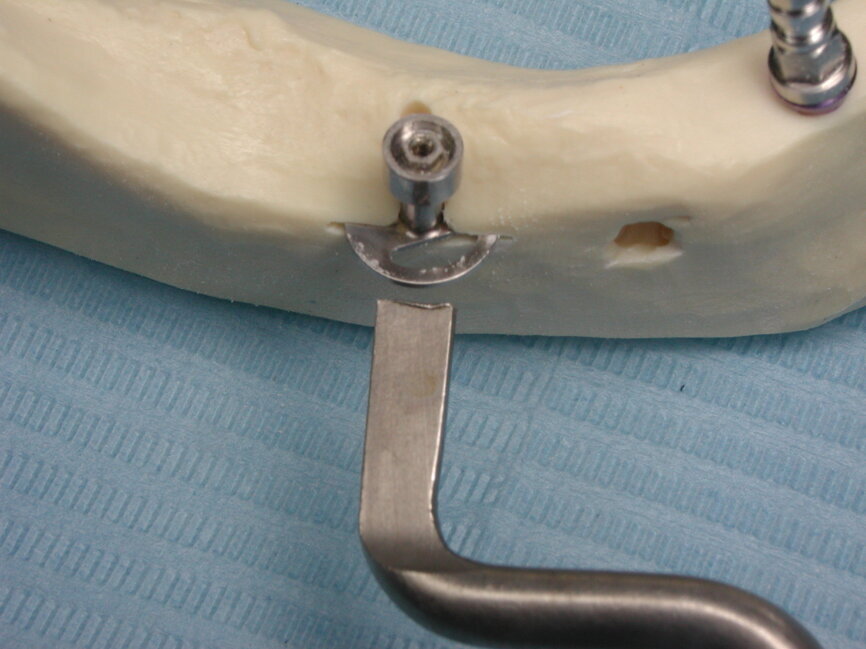

Au cours du temps, et avec la perte de l’organe dentaire, la crête alvéolaire va subir des modifications importantes, perdant progressivement sa hauteur, son épaisseur et sa densité. Lorsque la fonte osseuse se poursuit, l’osalvéolaire disparaît en quasi-totalité, laissant place à l’os basal qui constitue la structure matricielle de la face. Il ne reste que les piliers de la face essentiellement constitués d’os cortical : les piliers ptérygoïdiens, les piliers zygomatiques, les piliers canins et l’épine nasale. C’est à ce moment que l’implantologie basale prend tout son sens car cette discipline qui permet le plus souvent la mise en charge immédiate d’un bridge coulé vissé métal/résine, autorise une réhabilitation et une reprise fonctionnelle rapides en moins de quatre jours, (Fig 1)

Pour cela, elle fait appel à des implants spécifiques (Diskimplant : (Fig 2a, b)) permettant un ancrage dans l’os basal de la face, non soumis à la résorption, ainsi qu’à des techniques issues de la chirurgie maxillo- faciale.

Fig. 1 bridge coulé vissé métal - résine

Fig 2a : Implant spécifique : Diskimplant (Photo EPSON)

Fig.2b : implant spécifique : Diskimplant (Photo : EPSON )